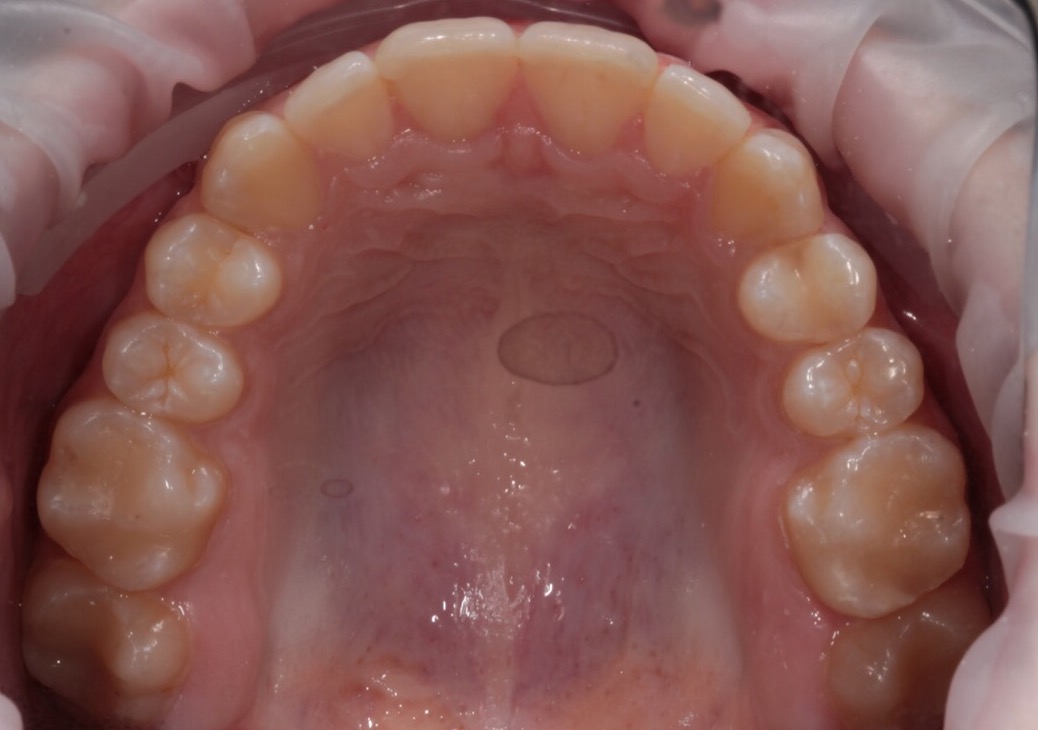

Invisalign состоит из набора индивидуальных, практически невидимых, съёмных капп(элайнеров), сменяемых 1 раз в 2 недели. Элайнеры за этот срок перемещают зубы до рассчитанного положения, после чего пациент меняет их на следующую пару.

В первый прием доктор снимает слепки с зубов пациента или делает сканирование(цифровой слепок)и отправляет их в лабораторию. Вместе со слепками или сканом доктор направляет специальную инструкцию, где подробно описывает все детали будущего лечения.

На основе этой инструкции и слепков в лаборатории создается план лечения (виртуальный 3D ролик) ClinCheck, где математически точно просчитываются степень воздействия на зубы, их направление перемещения и другие параметры. Пациент может сразу увидеть на компьютере, какой в итоге станет его улыбка и сколько по времени необходимо будет носить прозрачные каппы.